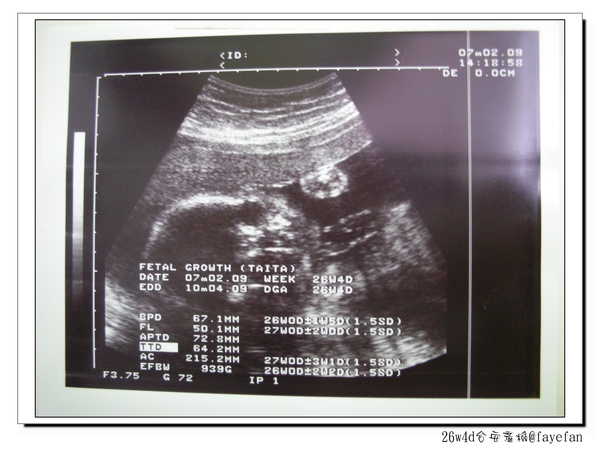

時間:2009年7月2日

地點:台安醫院

懷孕週期:26w4d

預產期:10月8日

不過寶貝一切正常

已經長到939公克了